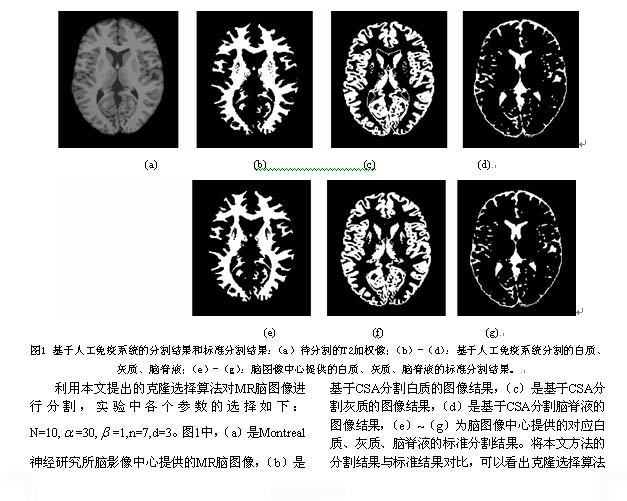

基于人工免疫系统的医学图像分割